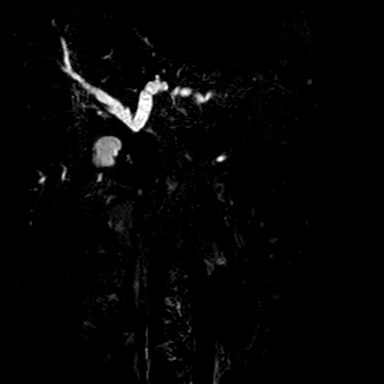

Octubre 2018. Hospital Italiano Paciente masculino de 47 años de edad acude ictérico a su control de anticoagulación oral.